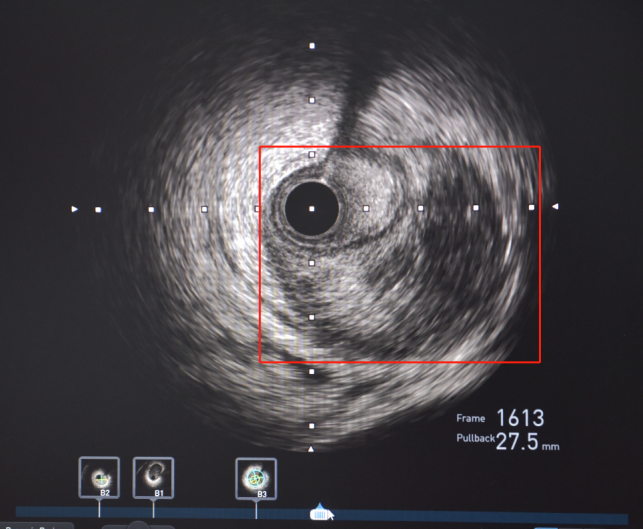

随后,患者立即被送往导管室,揭主任携副主任医师蒋溢为迅速给患者完成了冠脉造影,术中见患者左主干明显变窄,回旋支闭塞,血流TIMI0级,前降支次全闭塞,血流TIMI1级。但此时尚未能明确患者是否为冠脉痉挛或冠脉自发夹层,揭英纯和蒋溢为副主任医师当机立断,为患者快速完成了血管内超声检查,原来是冠状动脉自发夹层!考虑到患者冠脉已经闭塞,遂在IVUS指导下选择切割球囊精准对闭塞血管进行切割扩张,恢复回旋支及前降支正常血流。

左主干至回旋支、前降支自发性冠状动脉夹层、血肿压迫真腔